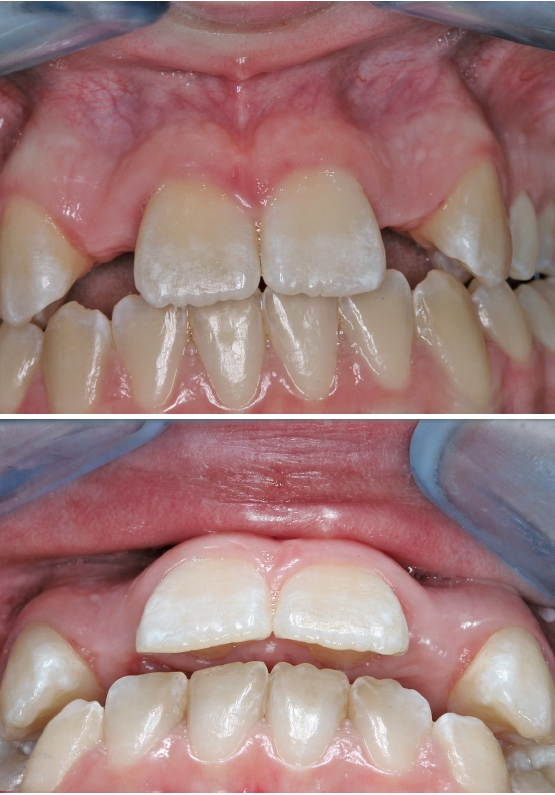

Nach viereinhalbmonatiger Einheilung der allogenen Knochenblöcke wurde wiederum ein Mukoperiostlappen mit einseitigem vertikalen Entlastungsschnitt gebildet und die Implantate prothetisch nach korrekter prothetischer Planung mit Hilfe einer Schablone in regio 12 und 22 inseriert (Abb. 9 und 10). Zur erneuten Auskonturierung wurden allogene Knochenspäne bukkal unter den Mukoperiostlappen geschoben und zur Weichgewebsaugmentation eine erneute autologe L-PRF-Membran nach Choukroun appliziert (Abb. 11 und 12). Abbildung 13 zeigt das postoperative OPG nach Insertion der beiden Implantate. Zur provisorischen Versorgung erhielt die Patientin wiederum beidseitig eine palatinal verklebte Maryland-Brücke regio 12 und 22.

Nach Aufschraubung des Smartpegs konnte mit dem Ostell Festigkeitswerte von 72 respektive 75 für die beiden Implantate regio 12 und 22 nach vier Monaten festgestellt werden, sodass die prothetische Versorgung zunächst mit Hilfe langzeitprovisorischer Kronen (Zirkonzahn Multistratum Flex) durchgeführt wurde (Abb. 14 und 15).

Nach weiterer mehrmonatiger Weichgewebsausformung durch die beiden Langzeitprovisorien 12 und 22 wurden dann reine Zirkoniumkronen zunächst provisorisch eingesetzt und die Patientin in die hauszahnärztliche Versorgung zurücküberwiesen (Abb. 16).